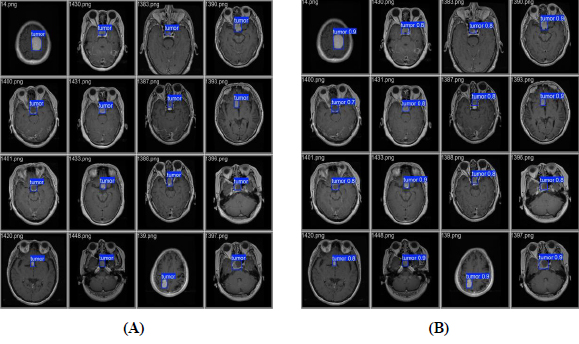

Validation and prediction batches for tumour detection (A) validation batch and (B) predication batch.

presents a visual comparison between the validation batch (Fig. 7A) and the prediction batch (Fig. 7B) generated by the YOLOv12 model. These batches are designed to improve computational efficiency and increase inference speed, facilitating the detection of tumors across various images. The validation images display tumor locations on the original images, whereas the predicted images show the model’s output after training. From this comparison, it can be concluded that YOLOv12 exhibits exceptional tumor detection performance, as evidenced by the accurate localization of tumors with bounding boxes and the corresponding confidence scores, closely aligned with the validation batch.